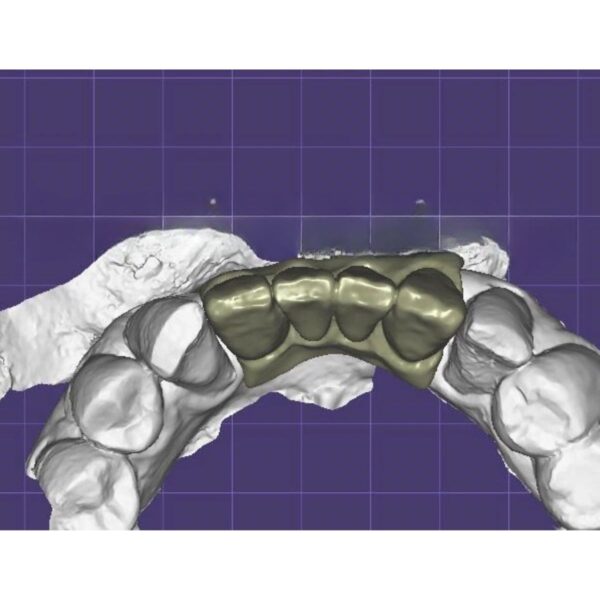

Screw-Retained Implant Crown Design Service (ASC Ready)

The safest solution for implant restorations. No cement, no worry.

- ✓ ASC Technology: Angulated Screw Channels (up to 25°) to hide access holes.

- ✓ Passive Fit: Perfect cement gap settings for Ti-Base bonding.

- ✓ Tissue Health: Custom emergence profile to shape the gingiva.